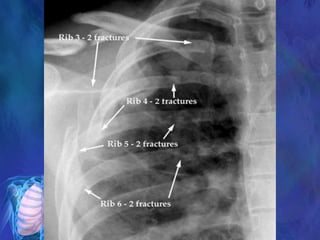

1. Multiple rib fractures? (Paradoxical respiration?)

2. Pneumothorax ? (subcutaneous emphysema?